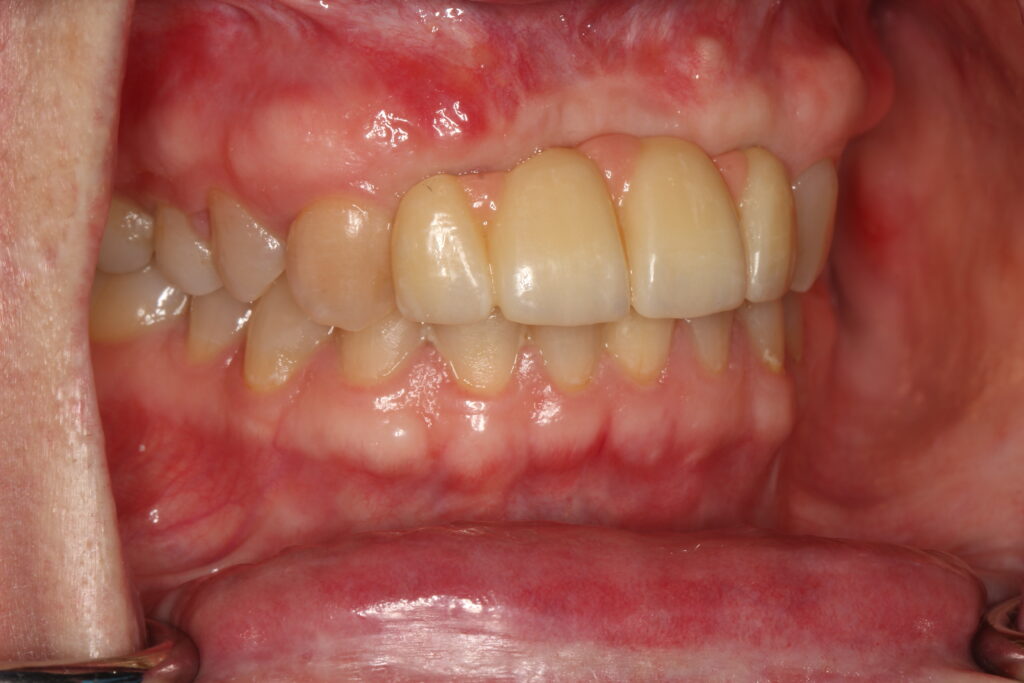

A selection of partial arch fixed implant bridge patients